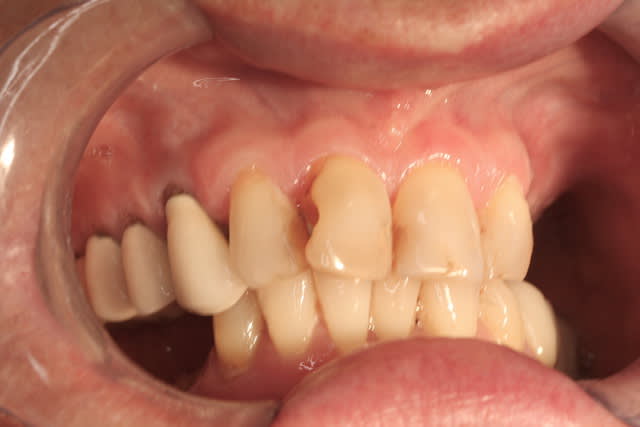

R29 uvltlt - Eugenol

R49 enunsh - Eugenol

R22 vkd0tr - Eugenol

R23 pmkimv - Eugenol

R26 gr1kkt - Eugenol

R34 w9wpow - Eugenol

Img 0052 dkvbyu - Eugenol

Leandro

28/02/2013 à 21h54

Joli travail!